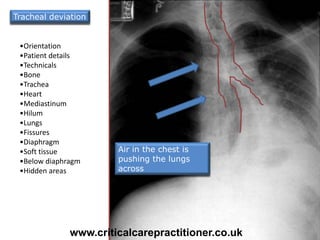

•Orientation

•Patient details

•Technicals

•Bone

•Trachea

•Heart

•Mediastinum

•Hilum

•Lungs

•Fissures

•Diaphragm

•Soft tissue

•Below diaphragm

•Hidden areas

Air in the chest is

pushing the lungs

across

Tracheal deviation